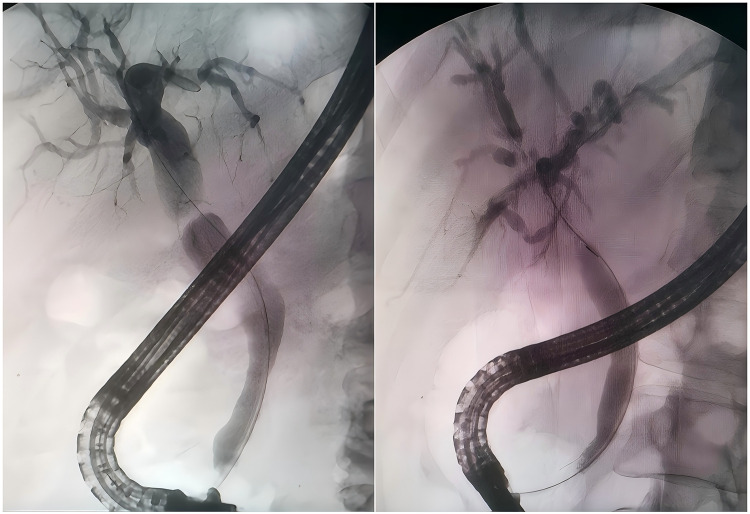

Purpose: The incidence of biliary stricture (BS) after liver transplantation (LT) significantly increases the risks of retransplantation and mortality. Although various endoscopic treatment strategies are available, a consensus is lacking in certain aspects, and the impact of endoscopic treatment on overall survival has yet to be studied. This retrospective study aims to explore factors influencing the efficacy of initial endoscopic treatment for BS after deceased donor orthotopic liver transplantation (OLT) and to analyze outcomes.

Patients and methods: This research conducted a retrospective analysis of 89 patients who developed BS after OLT at The First Hospital of Jilin University between 01/01/2014 and 01/01/2022. Patients were categorized into a successful group (59 patients) and a failed group (30 patients) based on the success or failure of initial endoscopic treatment. Risk factor analysis for initial endoscopic treatment failure in patients with BS after OLT was performed using univariate and multivariate logistic regression analysis. The survival analysis for patients with BS after OLT was conducted using Cox regression and Kaplan-Meier methods.

Results: The failure rate of initial endoscopic treatment was 33.7%. Independent risk factors for failure included the proximal and distal bile duct angle≤145 (OR=16.667, 95% CI: 3.279-83.333, P=0.001), severe stricture (OR=9.009, 95% CI: 1.590-50.000, P=0.013), and non-anastomotic stricture (NABS) type (OR=20.049, 95% CI: 2.663-150.953, P=0.004). Furthermore, failed initial endoscopic treatment (HR=3.205, 95% CI: 1.350-7.634, P=0.008) emerged as an independent risk factor for mortality in patients with BS after OLT.

Conclusion: Initial endoscopic treatment for BS in patients after OLT is effective, safe, and has a high success rate. However, patients with the proximal and distal bile duct angle≤145, NABS, and severe strictures exhibit poorer initial endoscopic treatment effect. Those whose initial endoscopic treatment fails demonstrate significantly worse prognoses.